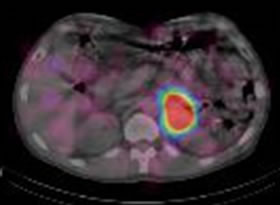

PET(ポジトロン断層画像)も核医学検査のひとつです。当院はサイクロトロン施設であり自前で18F-FDG(フルオロデオキシグルコース)を合成しPET検査を行っています。18F-FDGはブドウ糖に似た物質に放射性物質の18Fを付けたものです。注射をすると、ブドウ糖をよく使う脳・心筋・がんなどに集まります。この薬に使われる18Fは半減期が110分と短いため、すぐに減ってしまいます。そのため、病院内にサイクロトロンという機械を設置して病院内で製造しています。当院ではPETにCTを組み合わせたPET/CT検査を行っています。これによりPETの機能(糖代謝)画像とCTの形態画像との融合画像が得られ、診断精度の向上が図られます。

IVRは大きく、血管系、非血管系に分類できます。血管系IVRには血管拡張術、血管塞栓術などがあり、非血管系にはCTや超音波ガイド下の腫瘍生検やドレナージなどがあります。

千葉大学医学部附属病院放射線科では各科と協力しながら以下の様なIVRを行っています。